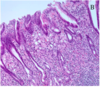

What is this showing?

Atypical ductal hyperplasia- is recognized by its histologic resemblance to ductal carcinoma in situ (DCIS). It consists of a relatively monomorphic proliferation of regularly spaced cells (with no overlap), sometimes with cribriform spaces.

Most surgeons will remove cells with atypical ductal hyperplasia